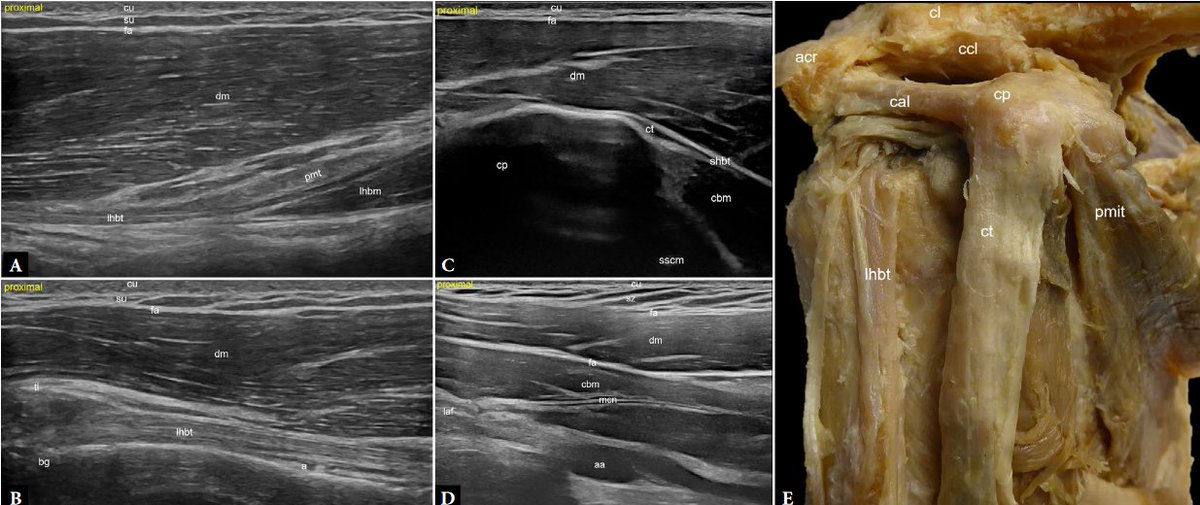

Advanced high-resolution musculoskeletal ultrasound: a histology- and anatomy-guided approach for improved imaging of the shoulder. Part 2: Anterior and lateral shoulder FREE DOWNLOAD: jultrason.pl/artykul.php?a=… FREE DOWNLOAD Part 1: x.com/Rheumatology/s… I would like to thank

Advanced high-resolution musculoskeletal ultrasound: a histology- and anatomy-guided approach for improved imaging of the shoulder.

Part 2: Anterior and lateral shoulder

FREE DOWNLOAD:

jultrason.pl/artykul.php?a=…

FREE DOWNLOAD Part 1:

x.com/Rheumatology/s…